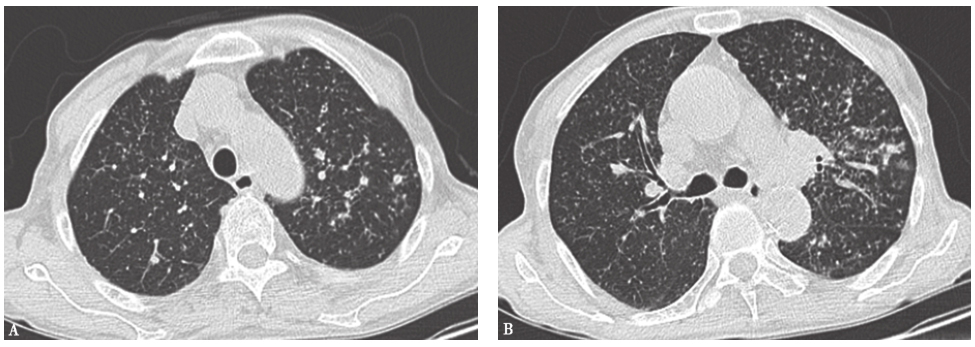

10天前胸部CT见双肺呈随机分布的弥漫性粟粒样小结节影(图2)。

图2 10天前胸部CT表现